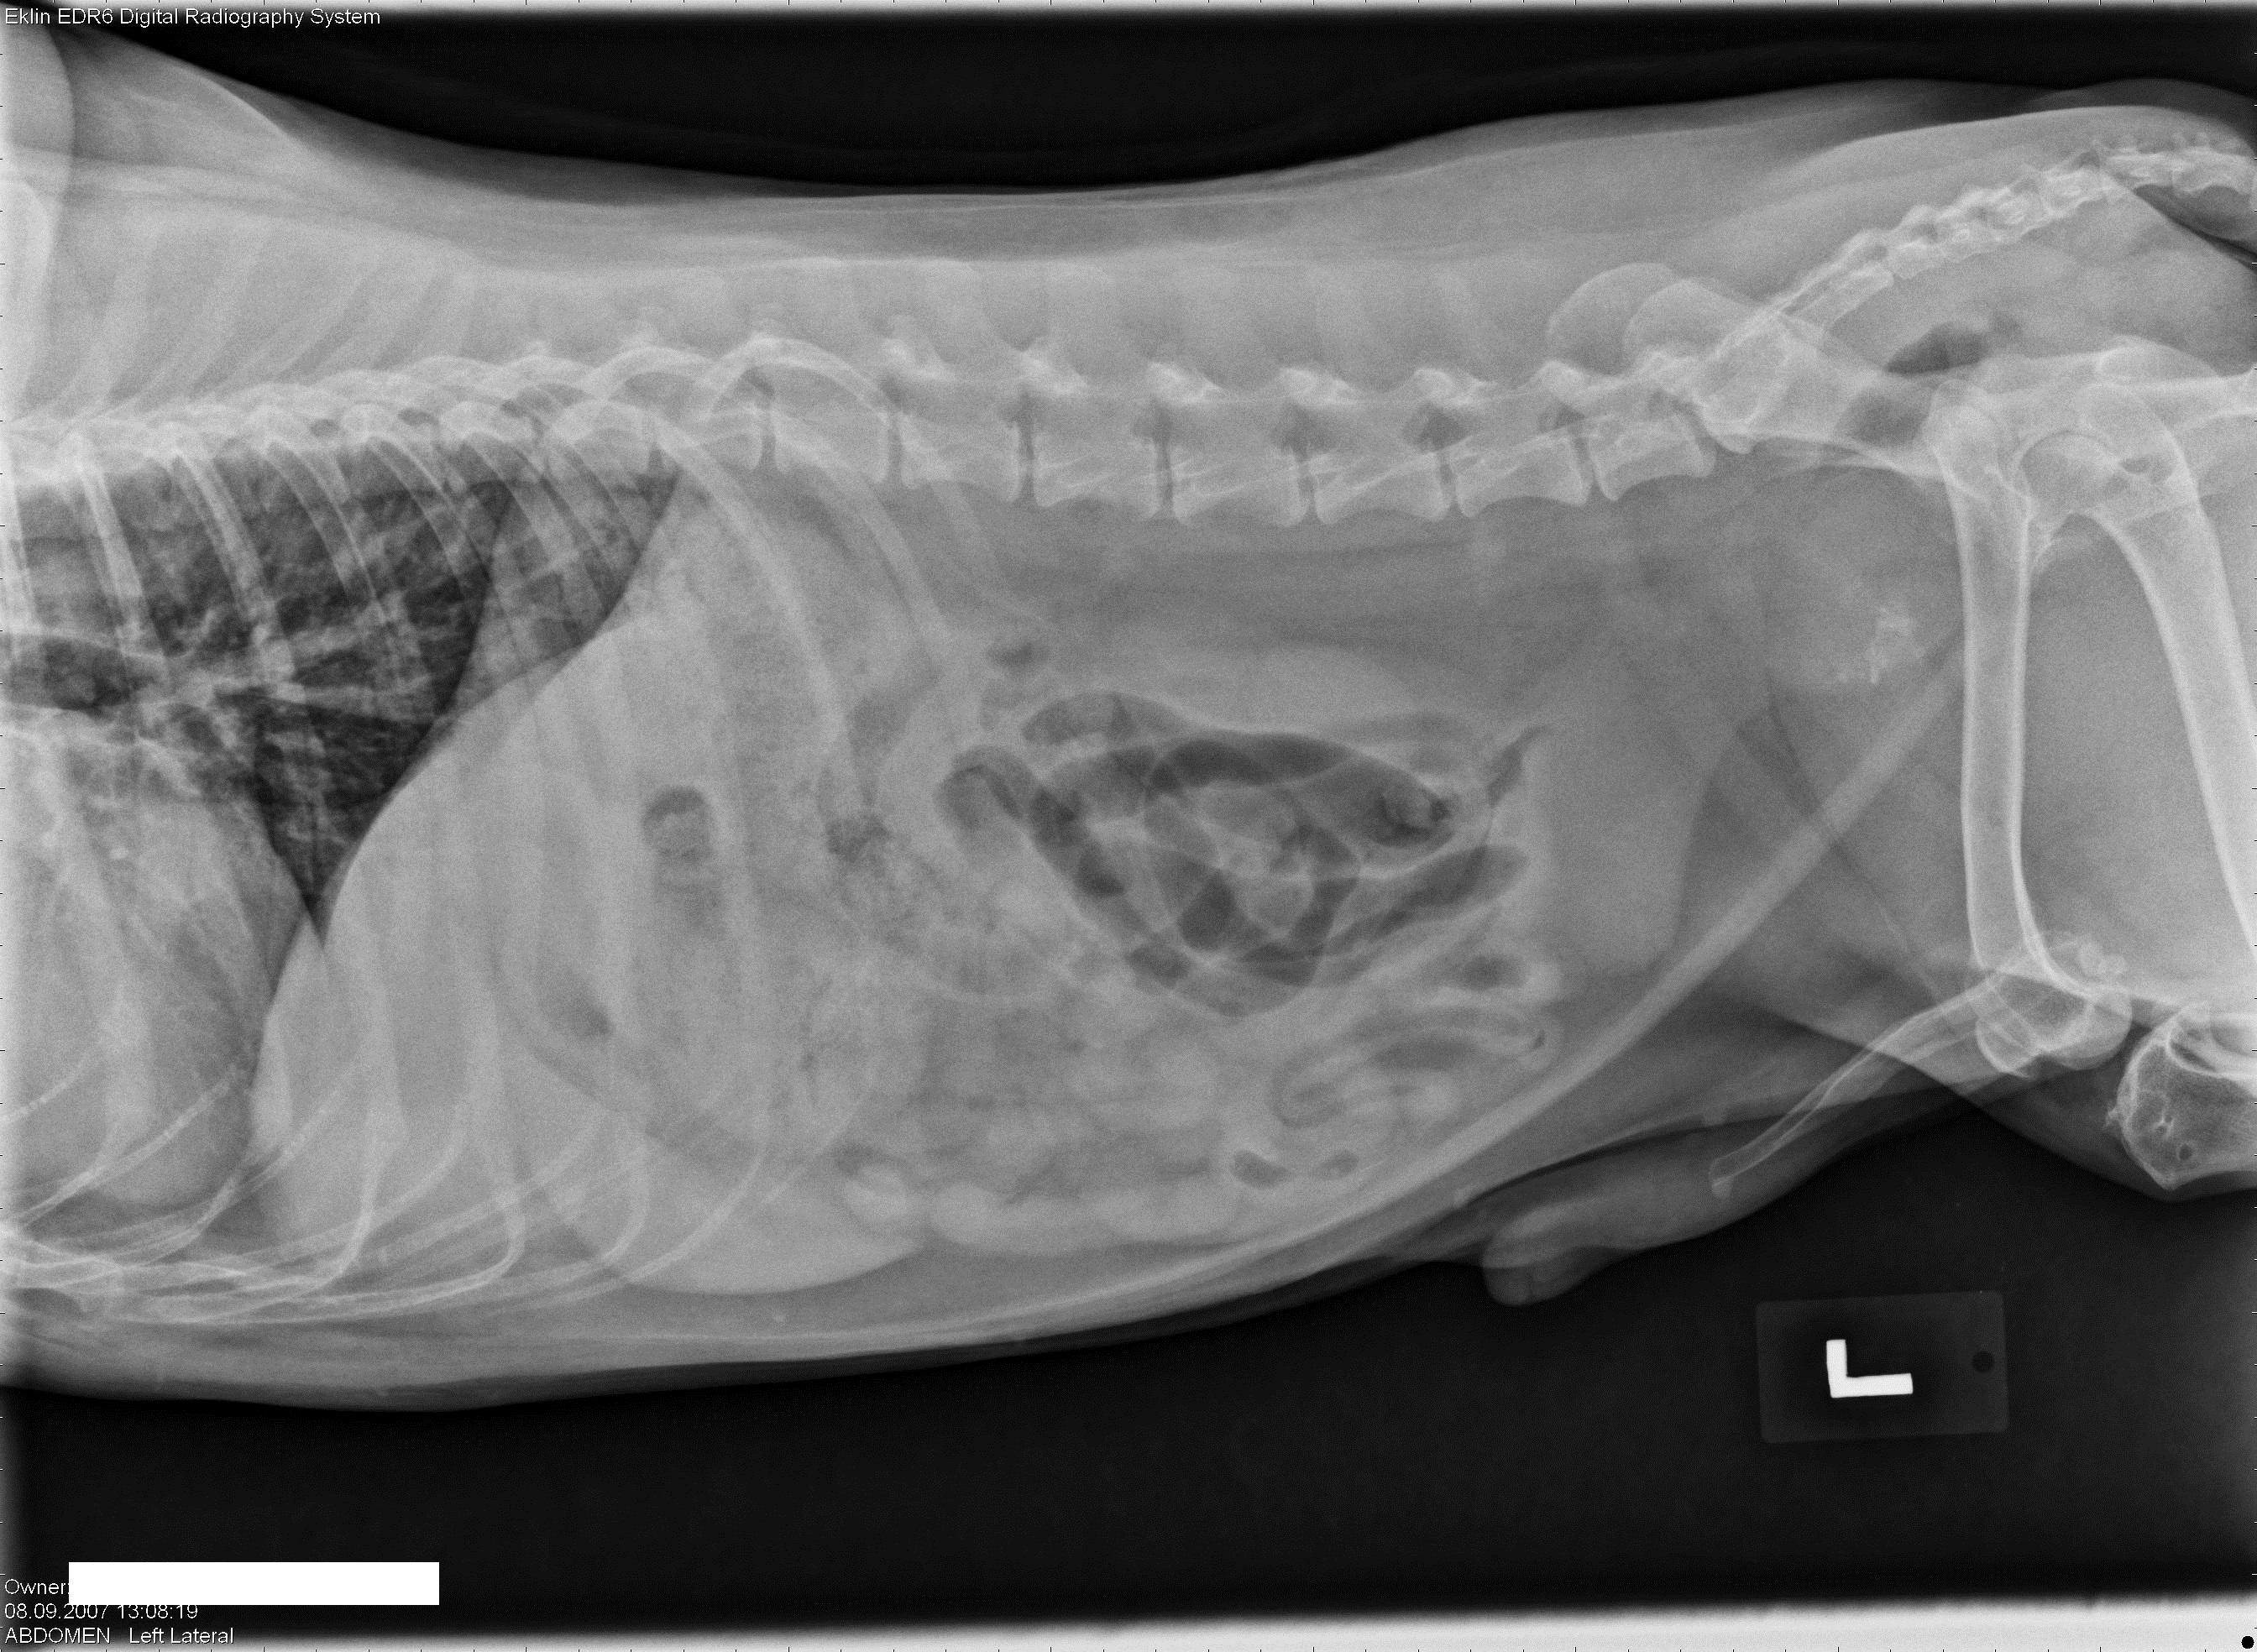

Een 10 jaar oude, mannelijk, gecastreerde hond wordt bij je aangeboden met erge tenesmus.Â

Hieronder vind je 5 Röntgen foto’s thorax en abdomen. Gebruik de pijltjes om erdoor te schuiven, of klik op de foto om te vergroten.